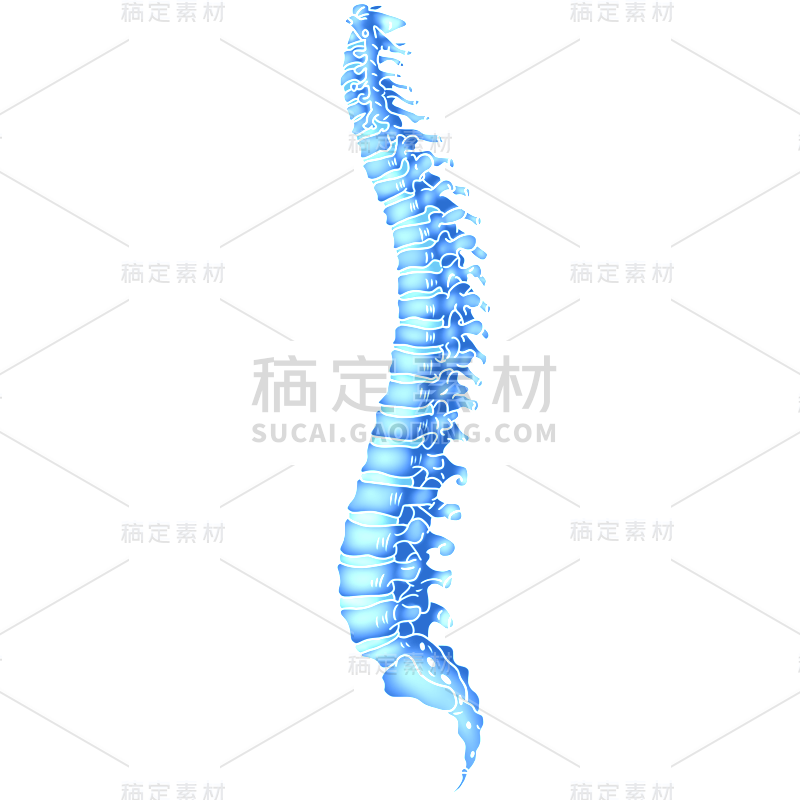

脊柱详情

EPS